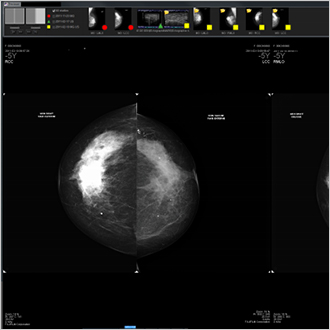

TM-Mammo

La solution TM-Mammo a été spécialement conçue pour répondre aux besoins en matière de stockage, de diffusion et de diagnostic de l'ensemble des images mammographiques numériques produites dans les services de sénologie. La visionneuse TM-Mammo permet de comparer facilement ces images avec l'historique multi-images de la patiente (toutes modalités confondues) et d'afficher des séquences d'affichage personnalisées. La tomosynthèse fait partie intégrante des rapports d'affichage.